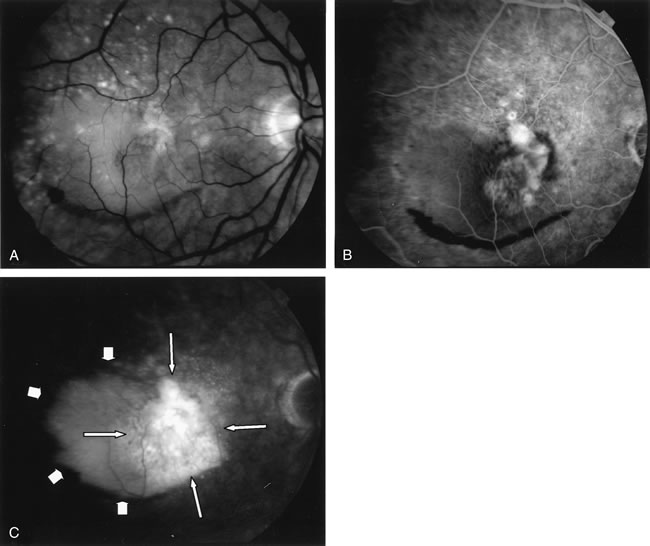

Gentamicin and tobramicin toxicity, which often result from inadvertent injection into the vitreous during cataract surgery, cause devastating retinal damage. In areas where high concentrations of gentamicin reach the retina there is obliteration of the retinal vasculature and ischemic necrosis of the retina (Fig. 43).269,270